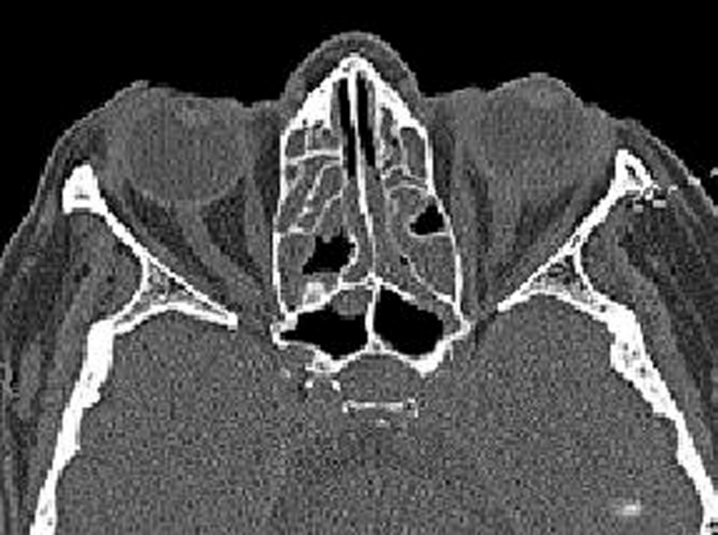

A 65-year-old woman with a two-month history of blurred vision, red eye and lid swelling in her left eye was referred to us. She was diagnosed to have exudative retinal detachment elsewhere and no clinical response could be achieved with prior systemic steroids. Our examination yielded no proptosis bilaterally and her motility was full. However conjunctival hyperemia, episcleral and conjunctival vessel engorgement were noted in OS (Figure 1 [Fig. 1]). Her best-corrected visual acuity was 20/20 in the right eye and 20/200 in the left eye. No relative afferent pupillary defect was noted. Color vision with Ishihara plates was 20/21 OD and 9/21 OS. Cornea was intact. Anterior chamber and vitreous were clear. Intraocular pressures with the Goldmann applanation tonometry were 12 and 14 mmHg in the right and left eyes respectively. While right fundus was normal fundus examination revealed a 360° exudative detachment in OS (Figure 2 [Fig. 2]). Computerized tomographic (CT) examination revealed chronic pansinusitis, left retinal detachment adjacent posterior scleritis, enlargement proximal optic nerve and retrobulbar striation due to cellulitis (Figure 3 [Fig. 3]). She was hospitalized and Ear Nose Throat (ENT) consultation was obtained. Pansinusitis with nasal polyps was diagnosed. Full systemic work-up was performed and no systemic disease was detected except the sinusitis. She was put on intravenous ceftriaxone and metronidazole. Conjunctival hyperemia and episcleral engorgement regressed and VA increased up to 20/70 in the left eye. Intravenous therapy was switched to oral sefuroxime and the patient was discharged. She returned one month later with decreased vision in her left eye again. She was experiencing pain with eyeball movements and the motility was also slightly restricted. This time visual acuity was hand motion in the OS and again there was 360° exudative detachment. She had a relative left afferent pupillary defect and color vision in the left eye was 0/21. She was readmitted and orbital CT was obtained again. Total paranasal sinus obliteration and scleral thickening was observed (Figure 4 [Fig. 4]). She was put on intravenous ceftriaxone and metronidazole and underwent sinus surgery and orbital decompression with polypectomy. Her visual acuity improved up to 20/100 two days after the surgery, stabilized at 20/30, exudative detachment had disappeared and no further recurrence occured during the follow-up of 10 months.

Figure 3: Axial non enhanced CT slice shows lost of the aeration in the ethmoidal sinuses and mucosal thickening in the sphenoid sinus revealed chronic sinusitis. On the left eye, retinal detachment and increased density and thickness in the adjacent sclera and optic nerve.